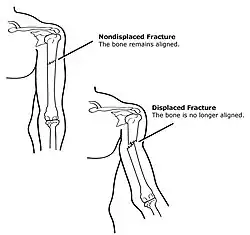

Reduction is a medical procedure to restore the correct anatomical alignment of a fracture or dislocation. When an injury results in a fracture, or broken bone, the bone segments can sometimes become misaligned. This is referred to as a displaced fracture, which requires the medical procedure called reduction.[1] Some providers may refer to this as 'setting the bone'. When an injury results in a dislocation of a joint, or the misalignment of two connecting bones,[2] a similar process of reduction must be performed to relocate the joint back into normal anatomical positioning. In the case of both displaced fractures and joint dislocation reduction is required for effective healing.